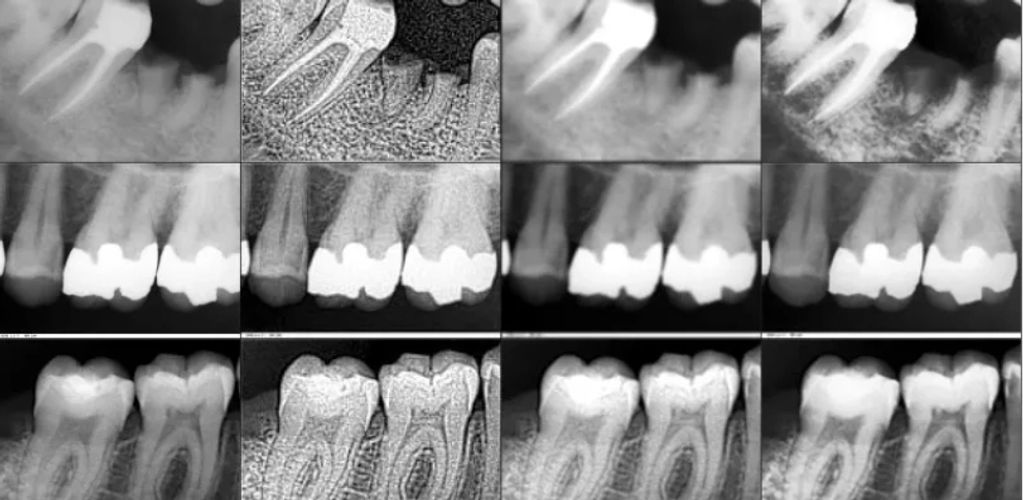

Digital intraoral X-rays are an advanced way of taking dental X-rays, where a small electronic sensor is placed inside the mouth to capture images of the teeth and surrounding bone. Unlike traditional film X-rays, digital X-rays use much less radiation and the images appear instantly on a computer screen. This allows dentists to quickly detect cavities, infections, bone loss, or other hidden prob